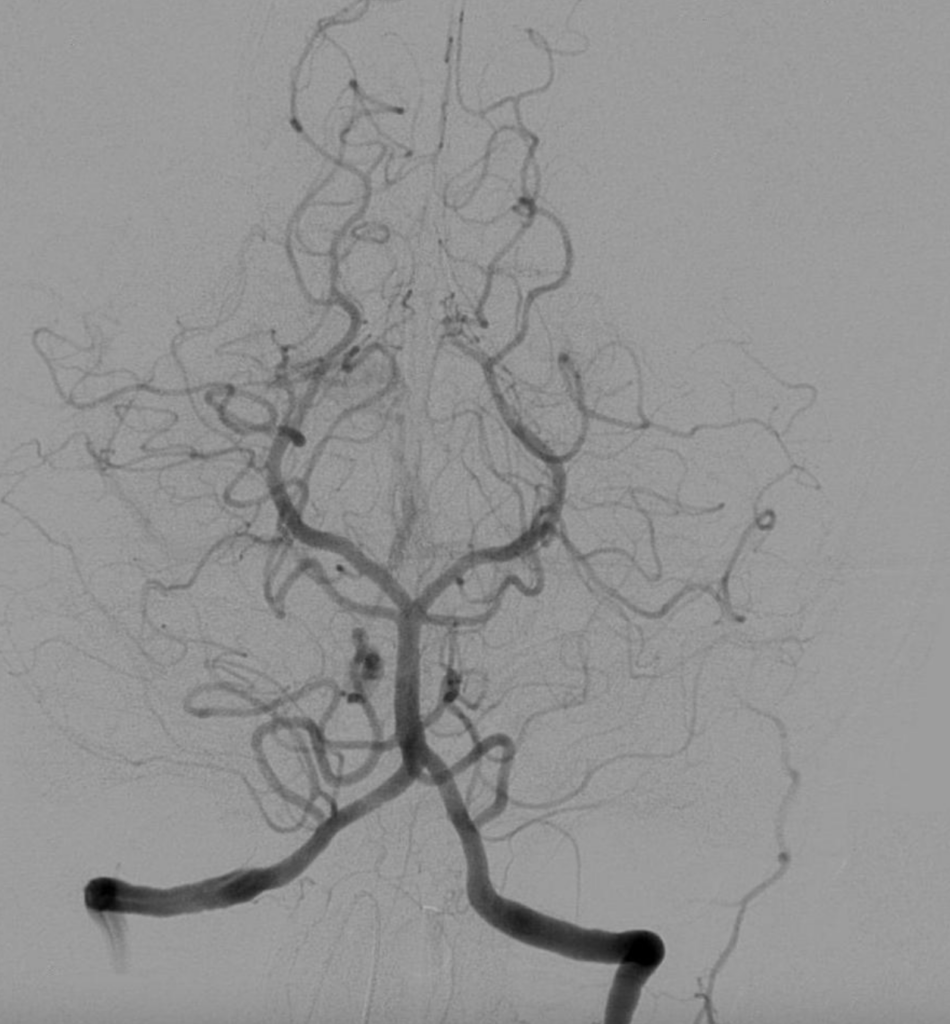

Angiografi jantung atau angiogram jantung adalah satu pemeriksaan yang penting untuk memeriksa keadaan pembuluh darah koroner dalam jantung.

Melalui prosedur angiografi jantung, doktor dapat menentukan jika terdapat penyumbatan dalam aliran darah yang menuju ke otot jantung.

Prosedur angiografi jantung, atau juga dikenali sebagai angiografi koroner, melibatkan penyuntikan cecair kontras ke dalam pembuluh darah jantung.

Dengan bantuan cecair kontras ini, mesin sinar-X akan menghasilkan siri gambaran yang jelas mengenai keadaan pembuluh darah jantung, termasuk aliran darahnya, dan menampilkannya pada skrin monitor.

- Cecair kontras disuntikkan melalui kateter ke dalam arteri dan bilik jantung untuk menjadikan pembuluh darah koroner jantung terlihat dengan jelas pada mesin sinar-X.

- Gambaran jantung pesakit diambil menggunakan mesin sinar-X.

Pada artikel Kosharga.my, nampak Angiogram jantung, juga dikenali sebagai angiogram koroner, adalah pemeriksaan penting untuk menilai keadaan pembuluh darah koroner dalam jantung.

Melalui penyuntikan cecair kontras ke dalam pembuluh darah jantung dan penggunaan sinar-X, doktor dapat melihat aliran darah dan keadaan pembuluh darah jantung pesakit.